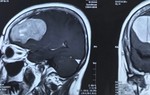

Trước đó, bệnh nhân được người nhà đưa đến BV trong tình trạng bị mù hẳn mắt phải, mắt còn lại bắt đầu kém đi. Theo bác sĩ Nguyễn Đức Anh, sau khi thăm khám, hình ảnh cắt lớp vi tính, hình ảnh cộng hưởng từ, các bác sĩ đã chẩn đoán bệnh nhân bị u màng não vùng trên yên. Do được phát hiện muộn, bệnh nhân đến viện đã mù hẳn một mắt, mắt còn lại bắt đầu kém đi, khối u xâm lấn vào mạch nuôi não.